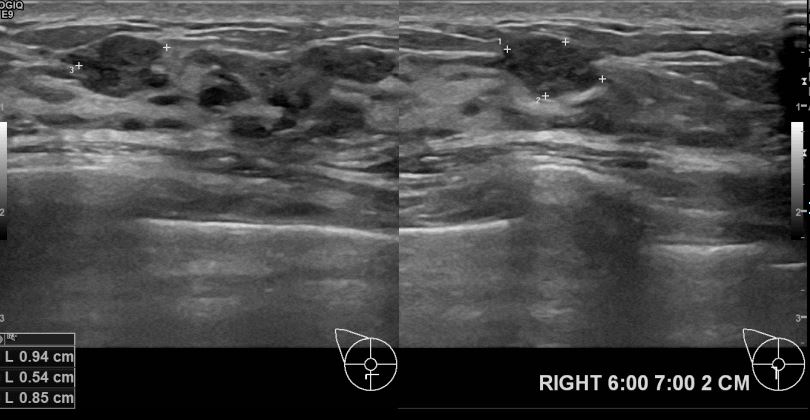

상기환자 3주전 부터 확인되는 유두분비물로 내원하신 30대 여성분으로 초음파검사후

의심스러운 우측유방혹 조직검사진행후 유방암 진단되셨읍니다